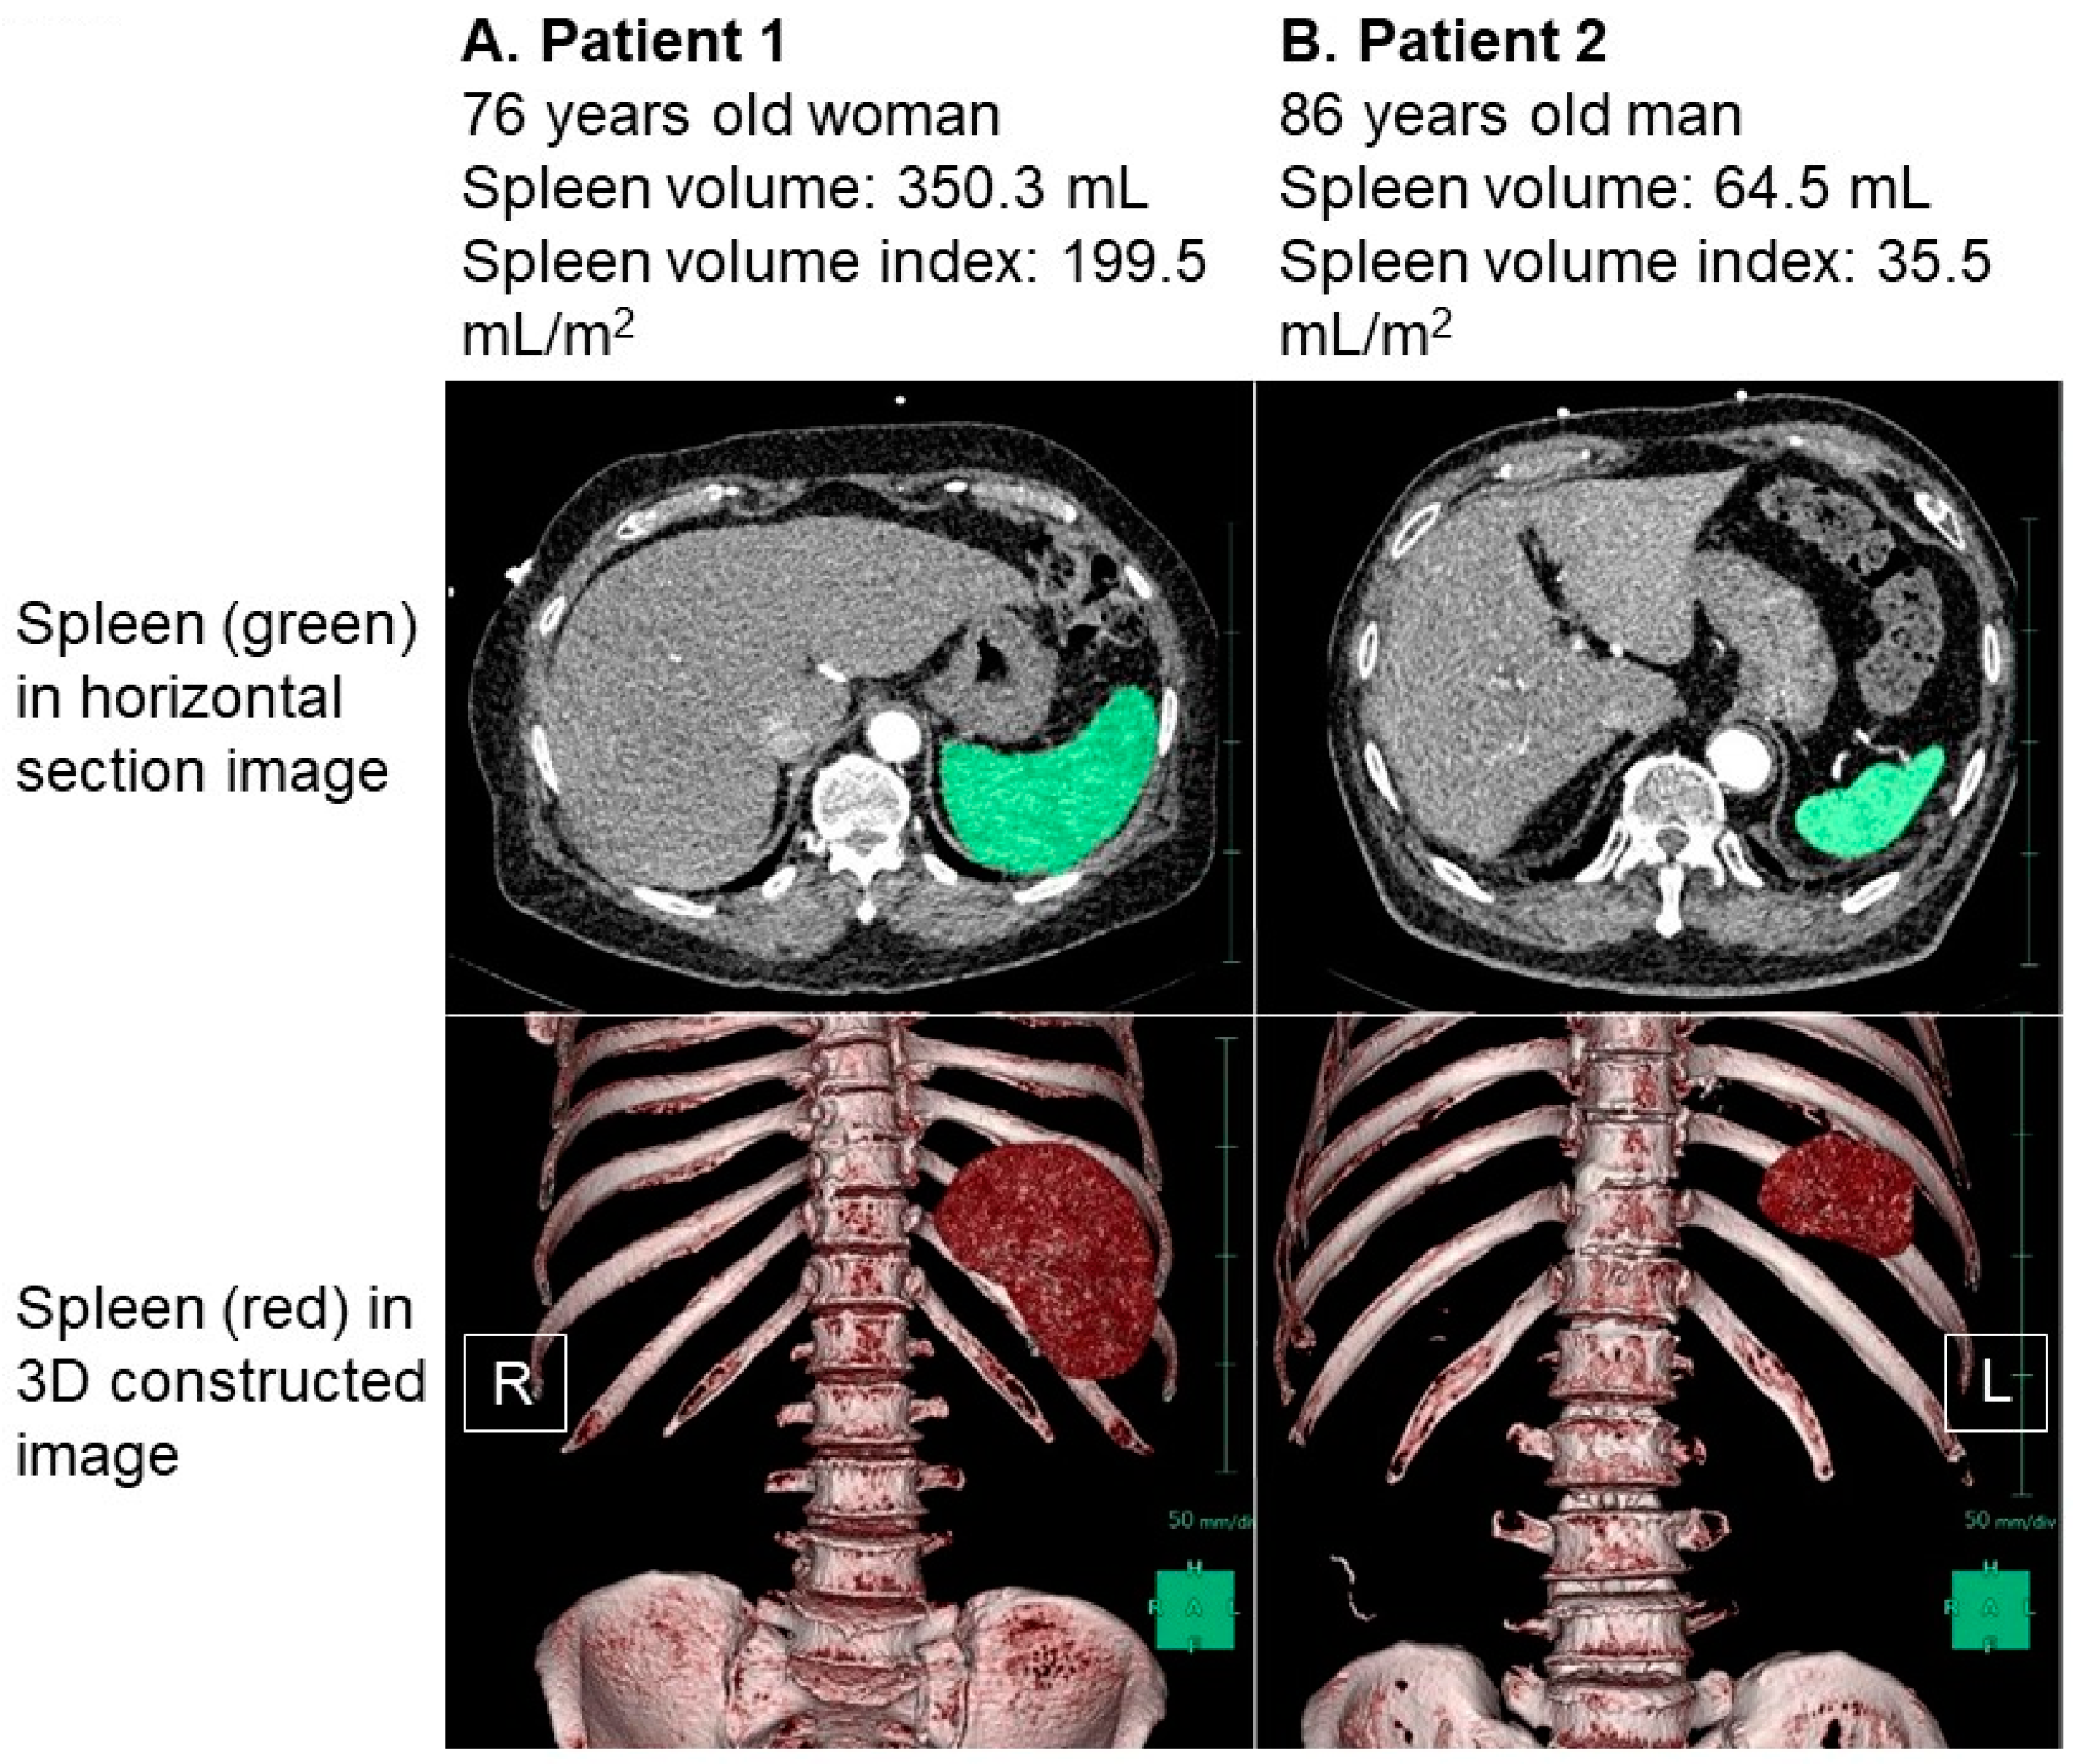

The distribution of the baseline SVI values exhibited considerable variability, with a median SVI of 65.5 (48.9, 86.9) mL/m2 (Figure 2). For illustrative purposes, representative cases of a low SVI and a high SVI were presented in Figure 3A and Figure 3B, respectively.

In Figure 3A, we observe a 76-year-old female patient who had a body height of 160 cm and a body weight of 72.3 kg, resulting in a body mass index of 28.2. Her splenic volume was measured at 350.3 mL, and when indexed to her body surface area, it amounted to 199.5 mL/m2. Figure 3B showcases an 86-year-old male patient with a body height of 161 cm and a body weight of 76.8 kg. His splenic volume was measured as 64.5 mL, and when indexed to his body surface area, it equated to 35.5 mL/m2.

As an illustrative example, the patient represented in Figure 3A, characterized by an elevated SVI, exhibited a plasma volume status of −9.5% and a cardiac index of 2.44 L/min/m2. In contrast, the patient illustrated in Figure 3B, with a low SVI, displayed a plasma volume status of −36.3% and a cardiac index of 1.93 L/min/m2.

Figure 3. Representative cases of high splenic volume index (A) and low splenic volume index (B). Spleen was colored in green in horizontal section image and was colored in red in three-dimensional constructed image. (A) Patient 1 was 76-year-old woman. Body height was 160 cm and body weight was 72.3 kg. Her splenic volume index was calculated as 199.5 mL/m2. (B) Patient 2 was 86-year-old man. His body height was 161 cm and body weight was 76.8 kg. His splenic volume index was calculated as 35.5 mL/m2. Splenic volume was larger in patient 1 compared to patient 2 in both 2-dimensional and 3-dimenstional imaging. R, right; L, left.